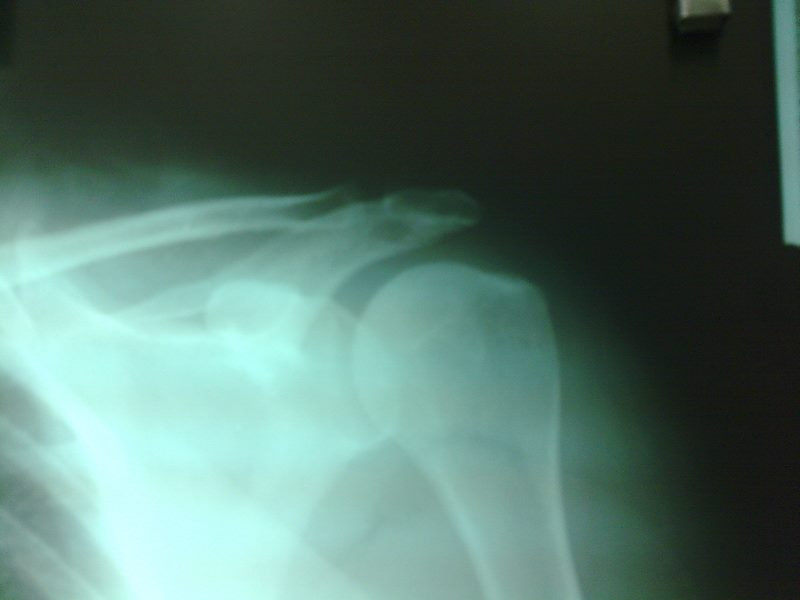

Radiografías con enfoque en fisiatría

Envíado por Dr. Hernán Darío Sánchez Ramos